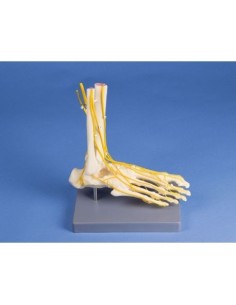

Dal cranio in 22 parti con incastri magnetici ai modelli di colonna vertebrale, da quelli di articolazioni a quelli di cuore, ogni pezzo della nostra collezione è progettato per un’immersione totale nello studio dell’anatomia umana. I nostri modelli, realizzati tramite scansioni di ossa vere, garantiscono un’esperienza tattile autentica e una fedeltà di peso quasi identica agli originali.